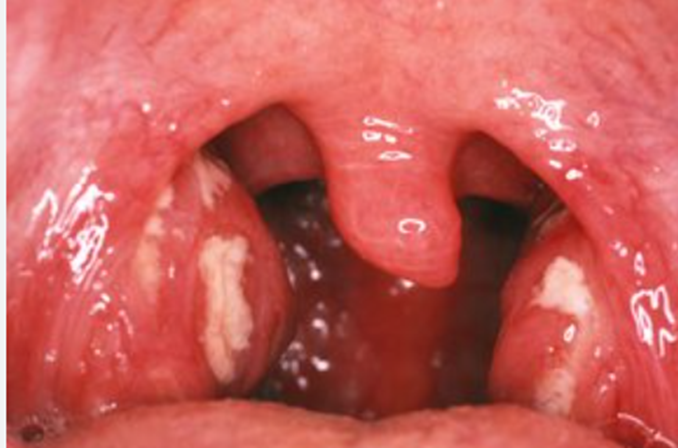

Figure – bilateral tonsillitis with exudate (taken from Tonsillitis - NHS (www.nhs.uk)

Background: Tonsillitis is very common, particularly among younger adults. Exudate is usually seen on the tonsils. The mainstay of management is analgesia, along with antibiotics. Steroids can also expedite patient recovery.